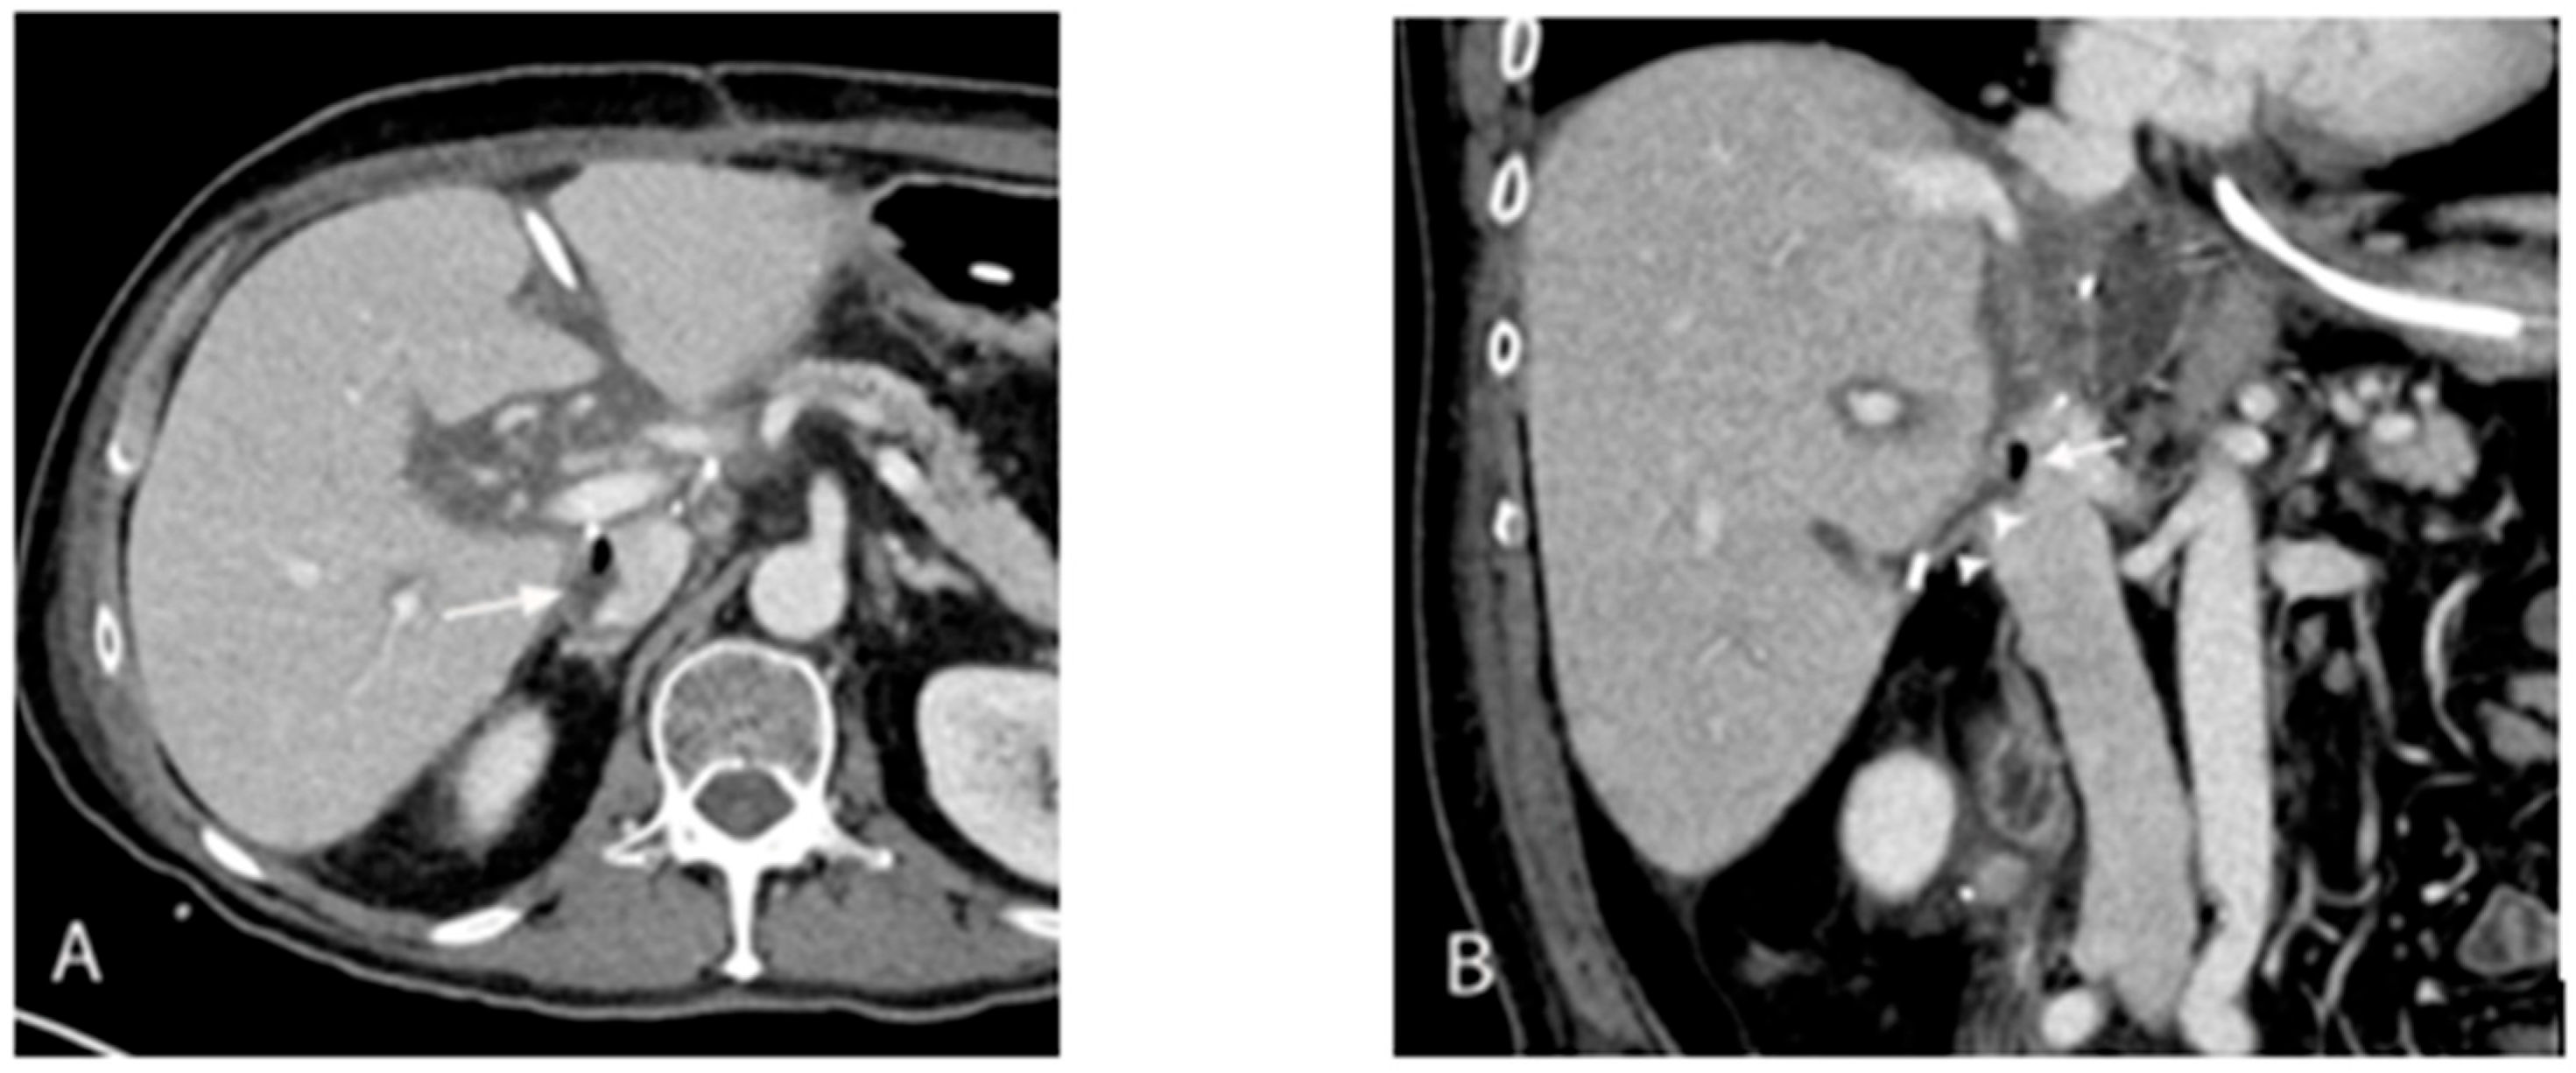

| Mid-August (Day 33) | CT: septic thrombophlebitis/enterocaval fistula from duodenal perforation → endoscopic closure with surgical clip | Bloodstream isolates showed daptomycin resistance on susceptibility testing. |